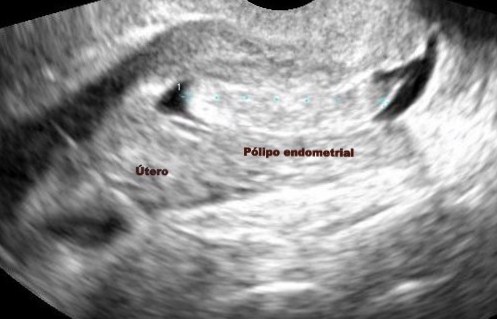

A continuación observamos una imagen obtenida en un estudio de histerosonografía donde se puede apreciar un pólipo endometrial:

El útero, se encuentra cubierto en su interior por una capa llamada“endometrio”. Cuando esta capa crece en un lugar específico se puede formar un “pólipo endometrial”.

El diagnóstico se realiza con un ultrasonido endovaginal y/o con un estudio que se llama «Histerosonografía».